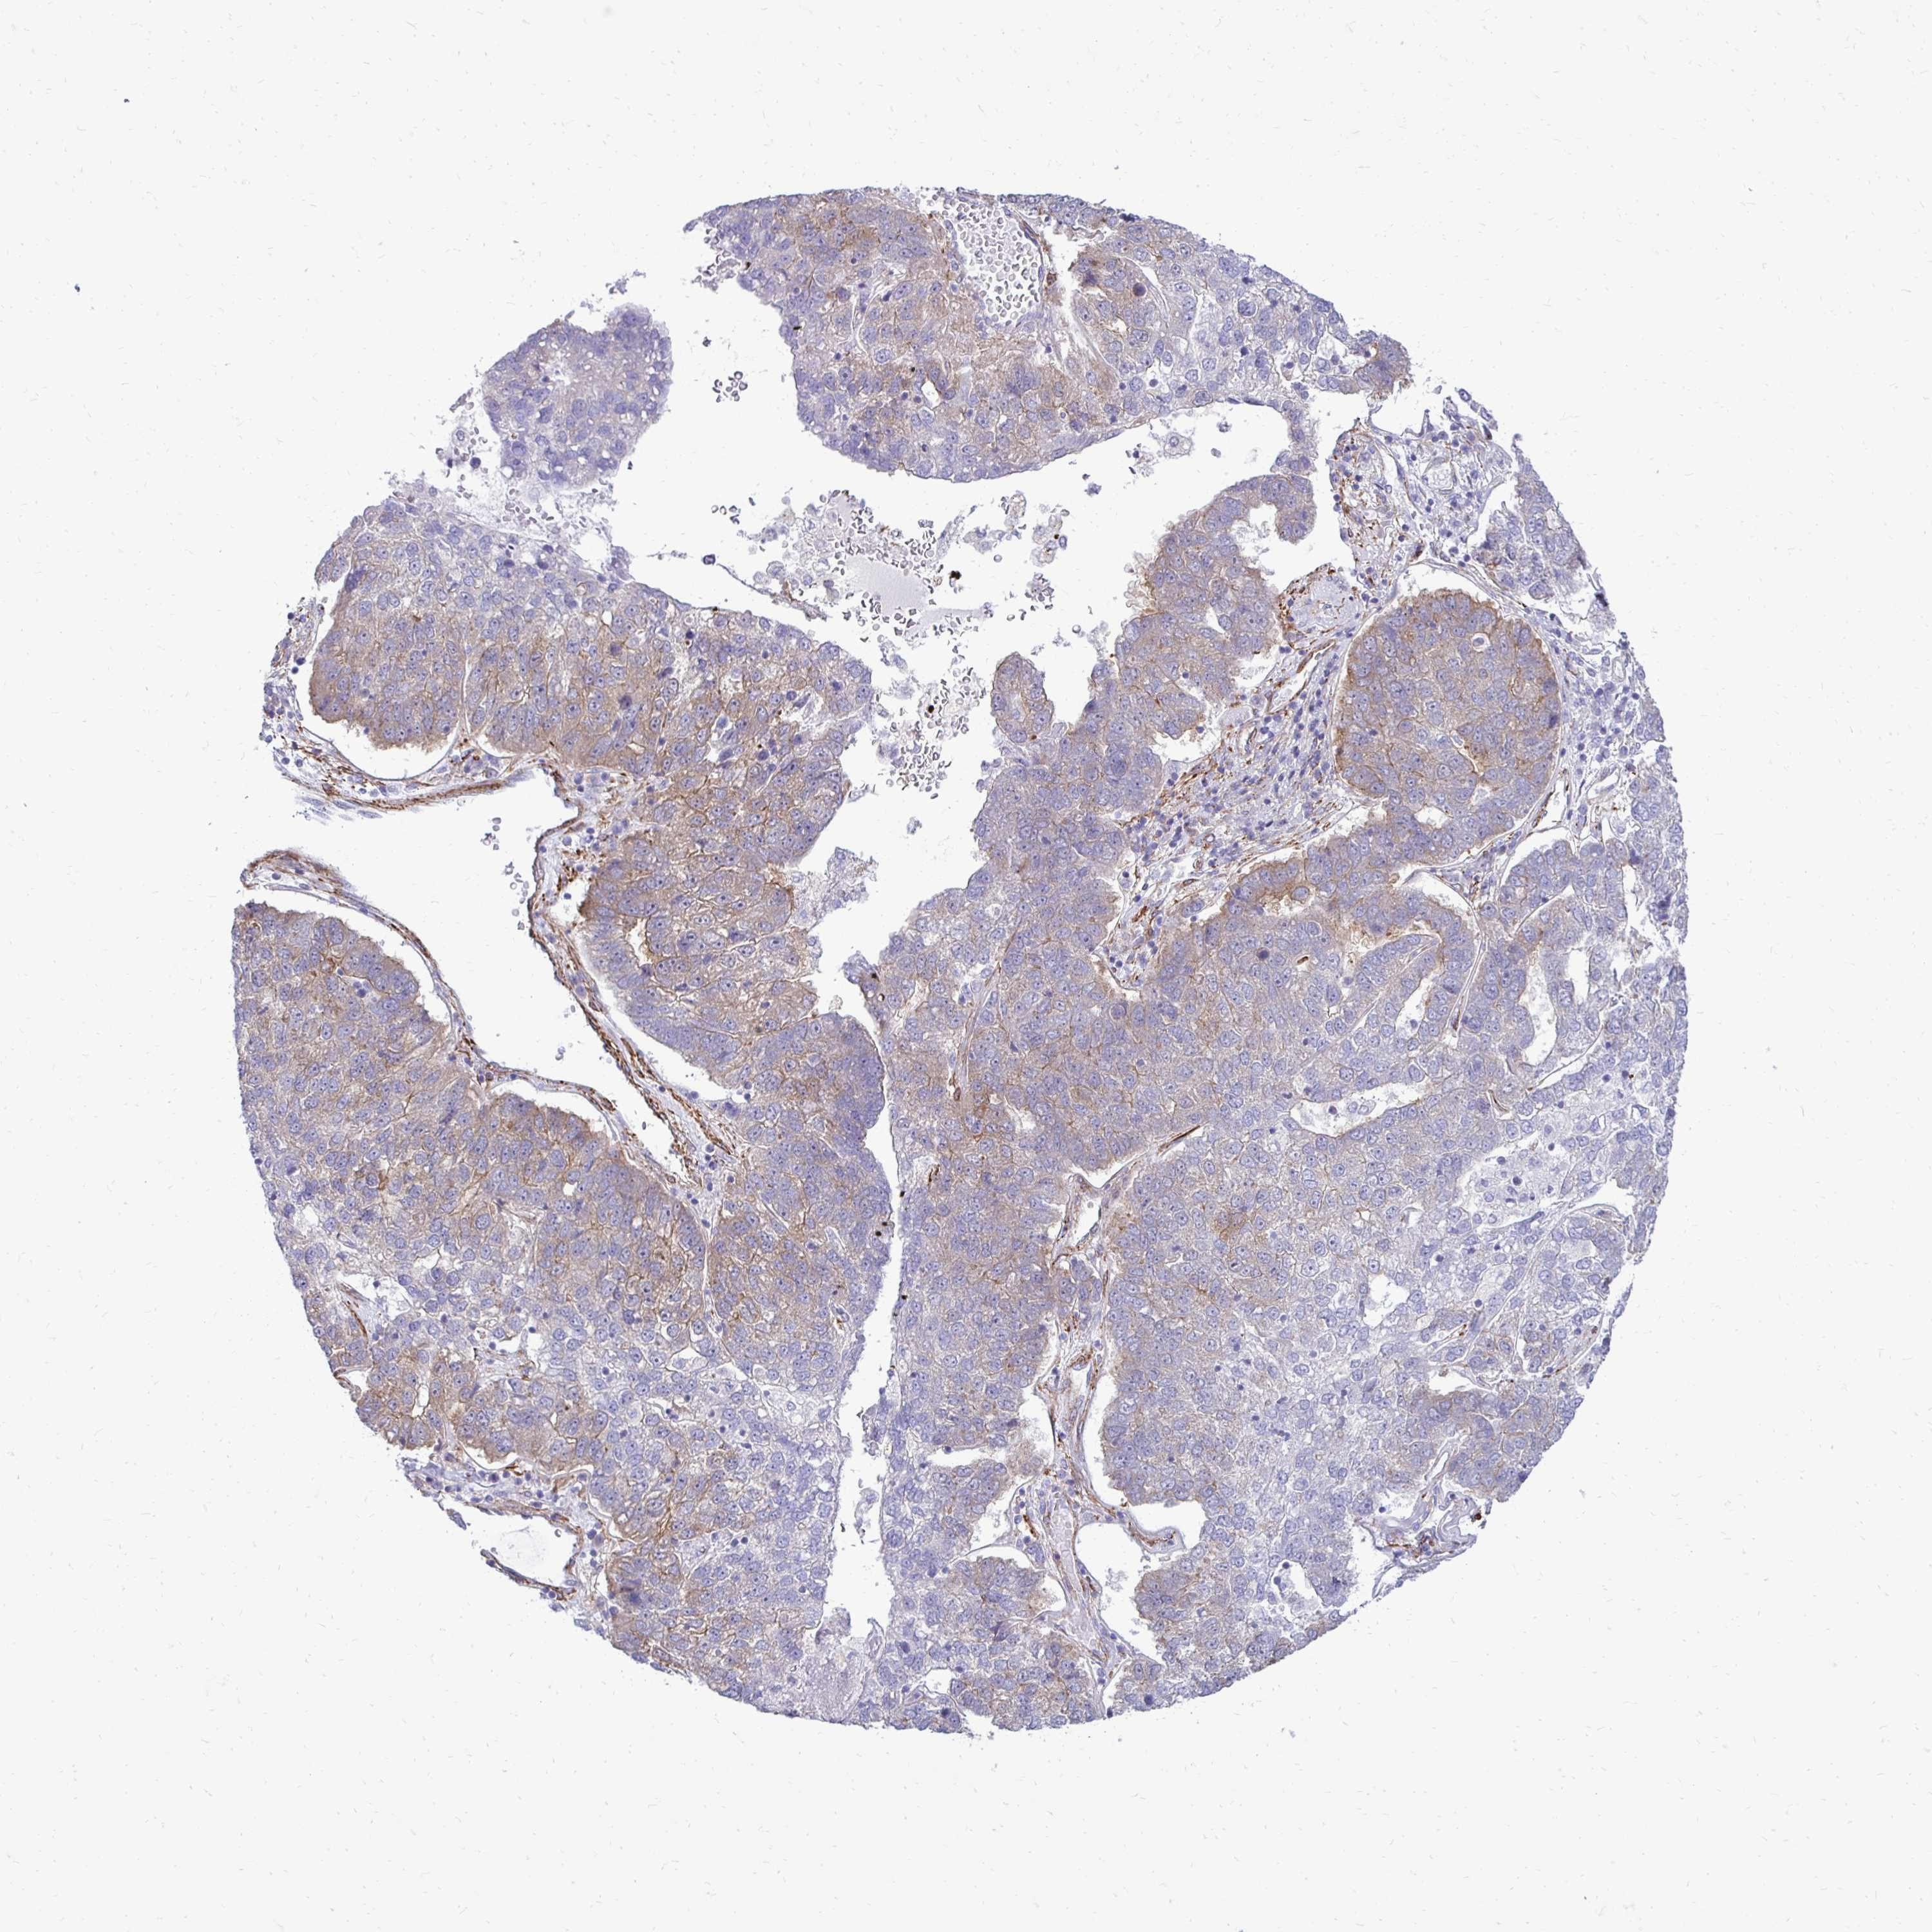

PANCREATIC CANCER - Protein expressioni

A mouse-over function shows sample information and annotation data. Click on an image to view it in a full screen mode. Samples can be filtered based on level of antibody staining by selecting one or several of the following categories: high, medium, low and not detected. The assay and annotation is described here.

Note that samples used for immunohistochemistry by the Human Protein Atlas do not correspond to samples in the TCGA dataset.

Antibody stainingi

Antibody staining in the annotated cell types in the current human tissue is reported as not detected, low, medium, or high, based on conventional immunohistochemistry profiling in selected tissues. This score is based on the combination of the staining intensity and fraction of stained cells.

Each image is clickable and will lead to virtual microscopy that enables deeper exploration of all samples and also displays staining intensity scores, fraction scores and subcellular localization as well as patient and tissue information for each sample.

Antibody HPA051322

Antibody CAB017111

Staining

High

Medium

Low

Not detected

Intensity

Strong

Moderate

Weak

Negative

Quantity

>75%

75%-25%

<25%

None

Location

Nuclear

Cytoplasmic/membranous

Cytoplasmic/membranous,nuclear

Adenocarcinoma, NOS